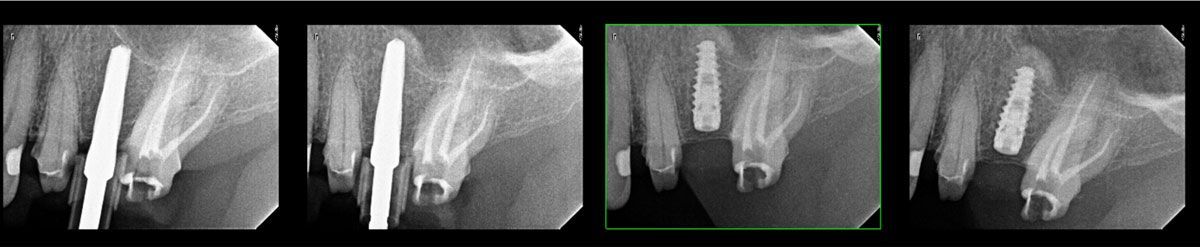

- Learn to plan implants using Blue Sky Plan

- Learn the scanning protocols needed to do any type of surgical guides, how to do them and when to use each one

- Gain hands on experience in planning several implant cases so that you become proficient with the software. This experience can be used in other implant planning software programs as well.

- Get very proficient with tooth supported and tissue supported surgical guides